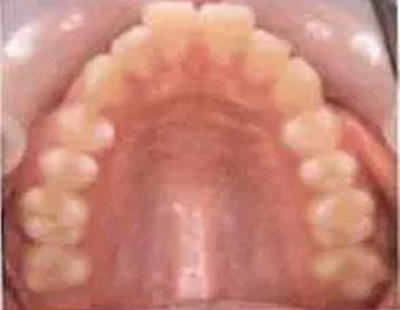

乳牙的晚期殘存(恒牙的先天性缺失)

[原因不明的多顆恒牙先天性缺失病例(17歲)]右下E殘存,

因為乳牙并不是搖搖欲墜的狀態(tài),所以最好讓醫(yī)生檢查下牙齦下面有沒有恒牙。

解說 確認是否是恒牙的先天性缺失

乳牙的晚期殘存有可能是恒牙的先天性缺失引起的。恒牙的先天性缺失有1、2顆牙缺失,也有好幾顆牙同時缺失的情況。數(shù)顆恒牙的缺失有可能是特定的先天性疾病(外胚層發(fā)育不良綜合征*1、色素失禁癥*2)引起的,需要加以注意。